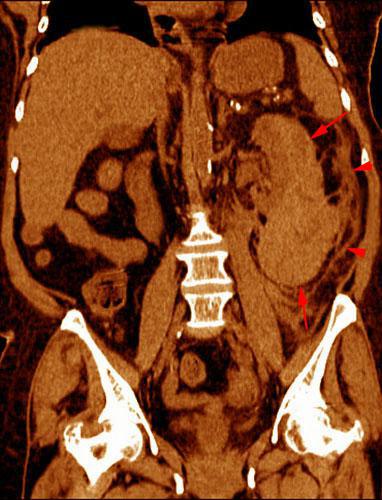

Hematoma subcapsular y perirrenal

VR seccional. Visión coronal anterior. Exploración no contrastada que muestra un hematoma subcapsular protuyendo en el espacio perirrenal (flechas). Obsérvese la infiltración hemática de la cápsula de Gerota (puntas de flecha)